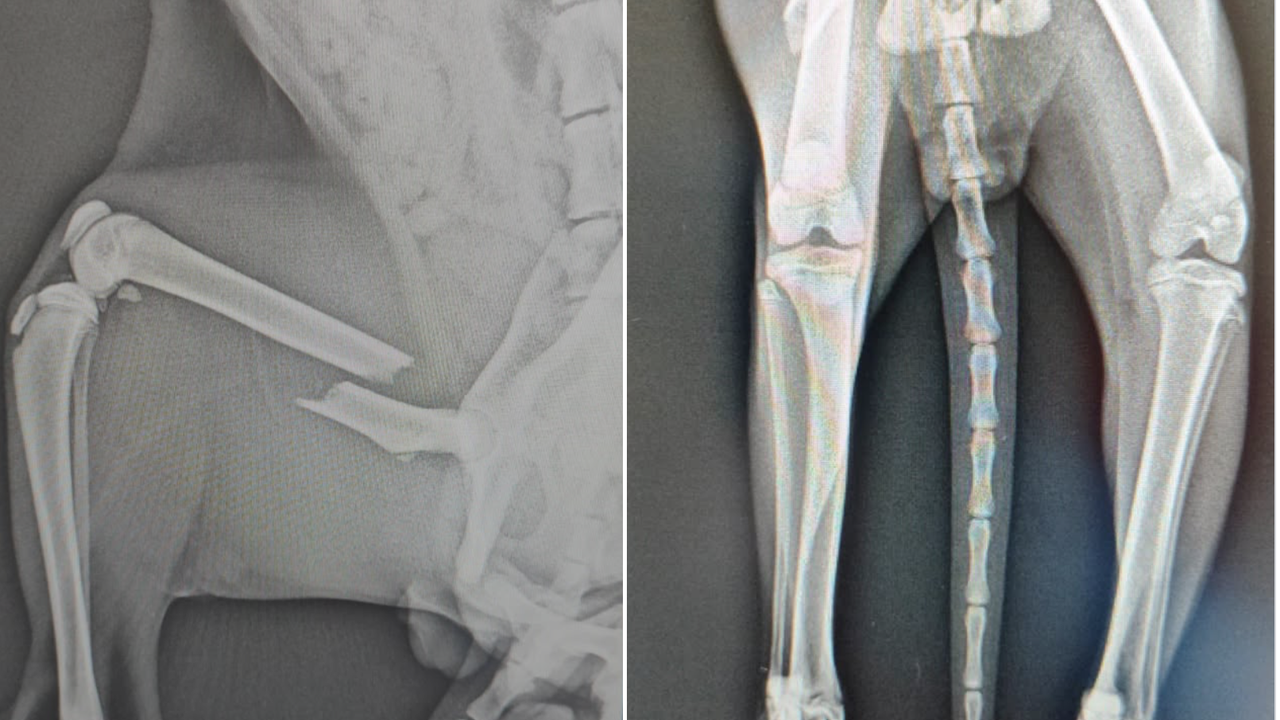

Hayvansever Figen Bilge, pazar bölgesinde araba çarpması sonucu ağır yaralı halde bulduğu yaklaşık 9 aylık bir kedi için acil destek çağrısında bulundu. “Limon” adını verdiği kedinin, veterinerde yapılan röntgenlerinde pelvis ve arka bacak bölgesinde ciddi kırıklar tespit edildiği belirtildi.

Bilge, Limon’un iyileşmesinin mümkün olduğunu ancak bunun için ortopedik cerrahi uzmanı tarafından yapılacak bir ameliyata ihtiyaç duyulduğunu ifade etti. Ameliyat sırasında plaka ya da pin uygulamasına karar verileceğini belirten Bilge, ameliyat ve tedavi süreci için acil olarak 50 bin TL gerektiğini açıkladı.